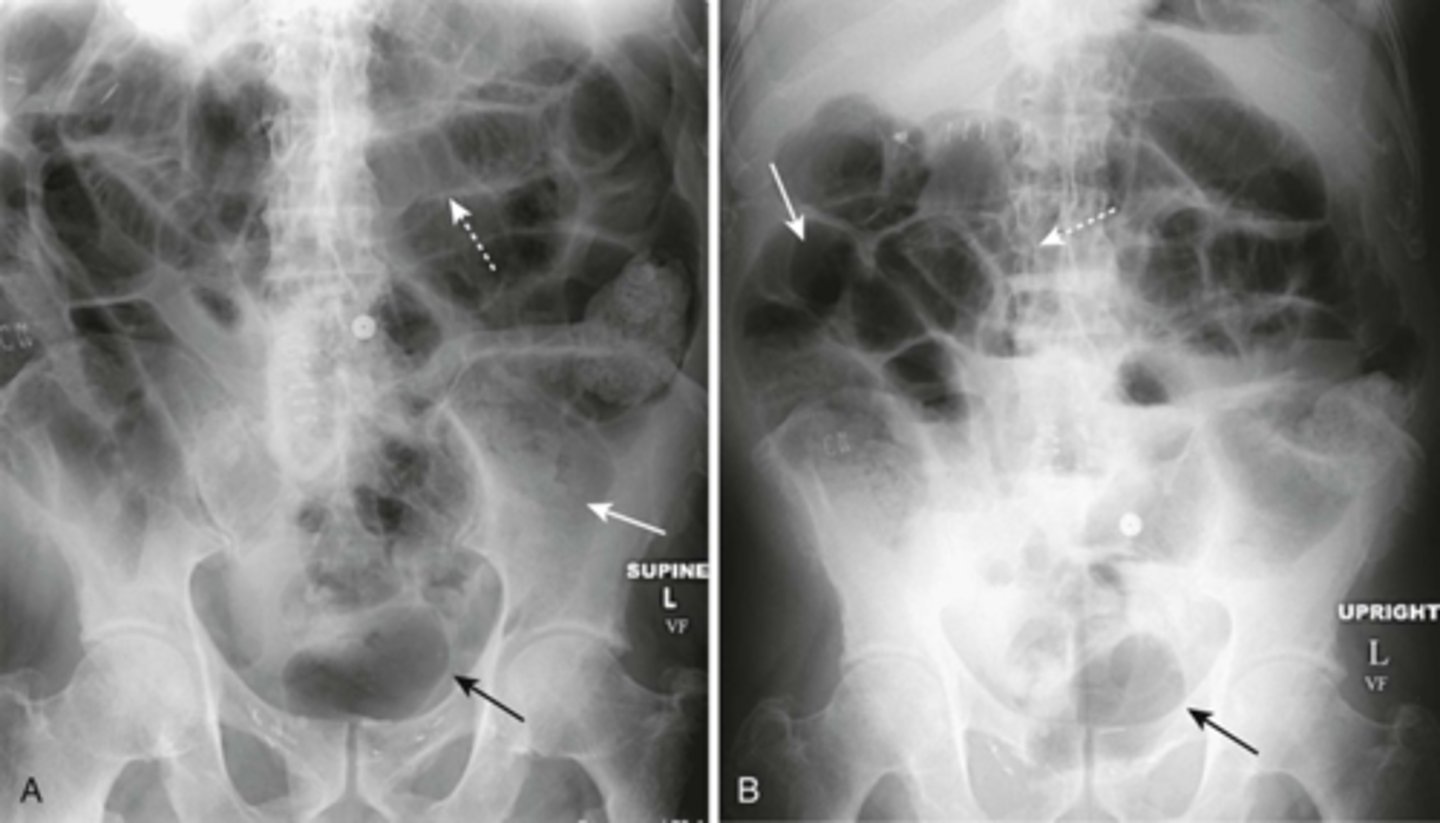

Generalized adynamic ileus, supine (A) and upright abdomen (B).

SOLID WHITE ARROWS: dilated loops of large bowel

DOTTED WHITE ARROWS: dilated loops of small bowel

SOLID BLACK ARROW: Rectum

Gas seen from small bowel to rectum. Patient had no bowel sound and had colon surgery the day before.